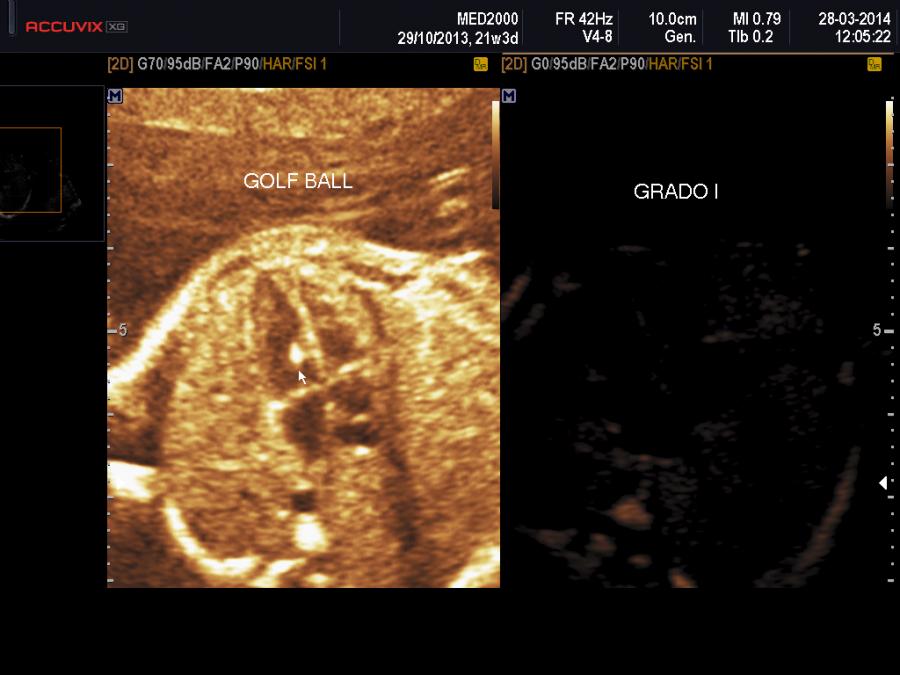

In base alla ecogenicità della golf ball rispetto ad una vertebra di riferimento si distinguono tre diversi gradi (Wax JR et al., 2003) che si ottengono riducendo il gain nel seguente modo:

1.     grado 1: scompare prima la golf ball e poi la vertebra

2.     grado 2: golf ball e vertebra scompaiono contemporaneamente

3.     grado 3: la golf ball scompare dopo la vertebra

Da alcuni studi sembra che il rischio di cromosomopatia aumenti in rapporto all'aumentare del grading (Wax JR et al., 2000).